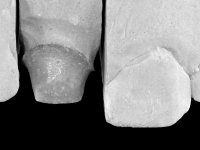

Male patient, 45 years old, smoker, with oesophageal reflux and poor oral hygiene. Teeth 11 and 21 presented an endodontic treatment and tooth 21 was rehabilitated with a Richmond type crown done 12 years ago. Tooth 11 presented an extensive restoration in composite resin in the buccal surface bonded exclusively to dentin. The palatal surface presented acid erosion and an extensive reconstruction in the endodontic access. The clinical crown was 4,5mm height and the root had 11mm.

An endodontic crown was proposed to the patient due to the reduced dimension of the clinical crown and the (almost) full absence of enamel. Two goals to be achieved:

The endocrown should be constructed with a zirconia framework with an ‘intra-root’ and crown components, being this last one veneered with ceramics.

After a previous dental impression in silicone to construct a provisional crown with the original shape, a tooth preparation was done following the principles of the Richmond crown. The intra-coronal preparation was done only until the enamel-cement line, without including the root.